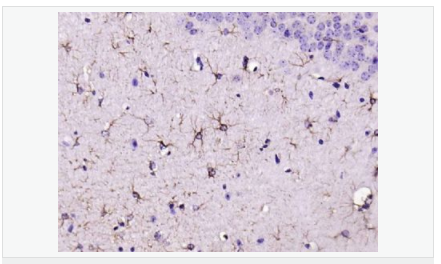

| 產(chǎn)品介紹 | This gene encodes one of the major intermediate filament proteins of mature astrocytes. It is used as a marker to distinguish astrocytes from other glial cells during development. Mutations in this gene cause Alexander disease, a rare disorder of astrocytes in the central nervous system. Alternative splicing results in multiple transcript variants encoding distinct isoforms. [provided by RefSeq, Oct 2008] Function: GFAP, a class-III intermediate filament, is a cell-specific marker that, during the development of the central nervous system, distinguishes astrocytes from other glial cells. Subunit: Interacts with SYNM. Isoform 3 interacts with PSEN1 (via N-terminus). Subcellular Location: Cytoplasm. Note=Associated with intermediate filaments. Tissue Specificity: Expressed in cells lacking fibronectin. Post-translational modifications: Phosphorylated by PKN1. DISEASE: Defects in GFAP are a cause of Alexander disease (ALEXD) [MIM:203450]. Alexander disease is a rare disorder of the central nervous system. It is a progressive leukoencephalopathy whose hallmark is the widespread accumulation of Rosenthal fibers which are cytoplasmic inclusions in astrocytes. The most common form affects infants and young children, and is characterized by progressive failure of central myelination, usually leading to death usually within the first decade. Infants with Alexander disease develop a leukoencephalopathy with macrocephaly, seizures, and psychomotor retardation. Patients with juvenile or adult forms typically experience ataxia, bulbar signs and spasticity, and a more slowly progressive course. Similarity: Belongs to the intermediate filament family. SWISS: P14136 Gene ID: 2670 Database links: Entrez Gene: 2670 Human Entrez Gene: 14580 Mouse Omim: 137780 Human SwissProt: P14136 Human SwissProt: P03995 Mouse Important Note: This product as supplied is intended for research use only, not for use in human, therapeutic or diagnostic applications. 星形膠質(zhì)細胞標志物 (Astrocyte Marker) GFAP是一個(gè)56kDa的中間絲蛋白(intermediate filament,IF),在中樞神經(jīng)系統發(fā)育期是一個(gè)特異性的標志物,以區別星形細胞和其它膠質(zhì)細胞。GFAP表達在皮層和海馬,急、慢性皮質(zhì)酮治療時(shí)表達減少。 GFAP可以和人、大鼠、小鼠的GFAP反應,在正常和腫瘤性的星形膠質(zhì)細胞陽(yáng)性表達,而神經(jīng)節細胞、神經(jīng)元、成纖維細胞、少突膠質(zhì)細胞和這些細胞來(lái)源的腫瘤細胞陰性表達,主要用于星形膠質(zhì)瘤等中樞神經(jīng)系統腫瘤的診斷和鑒別診斷,GFAP的缺乏可導致AD病。 |